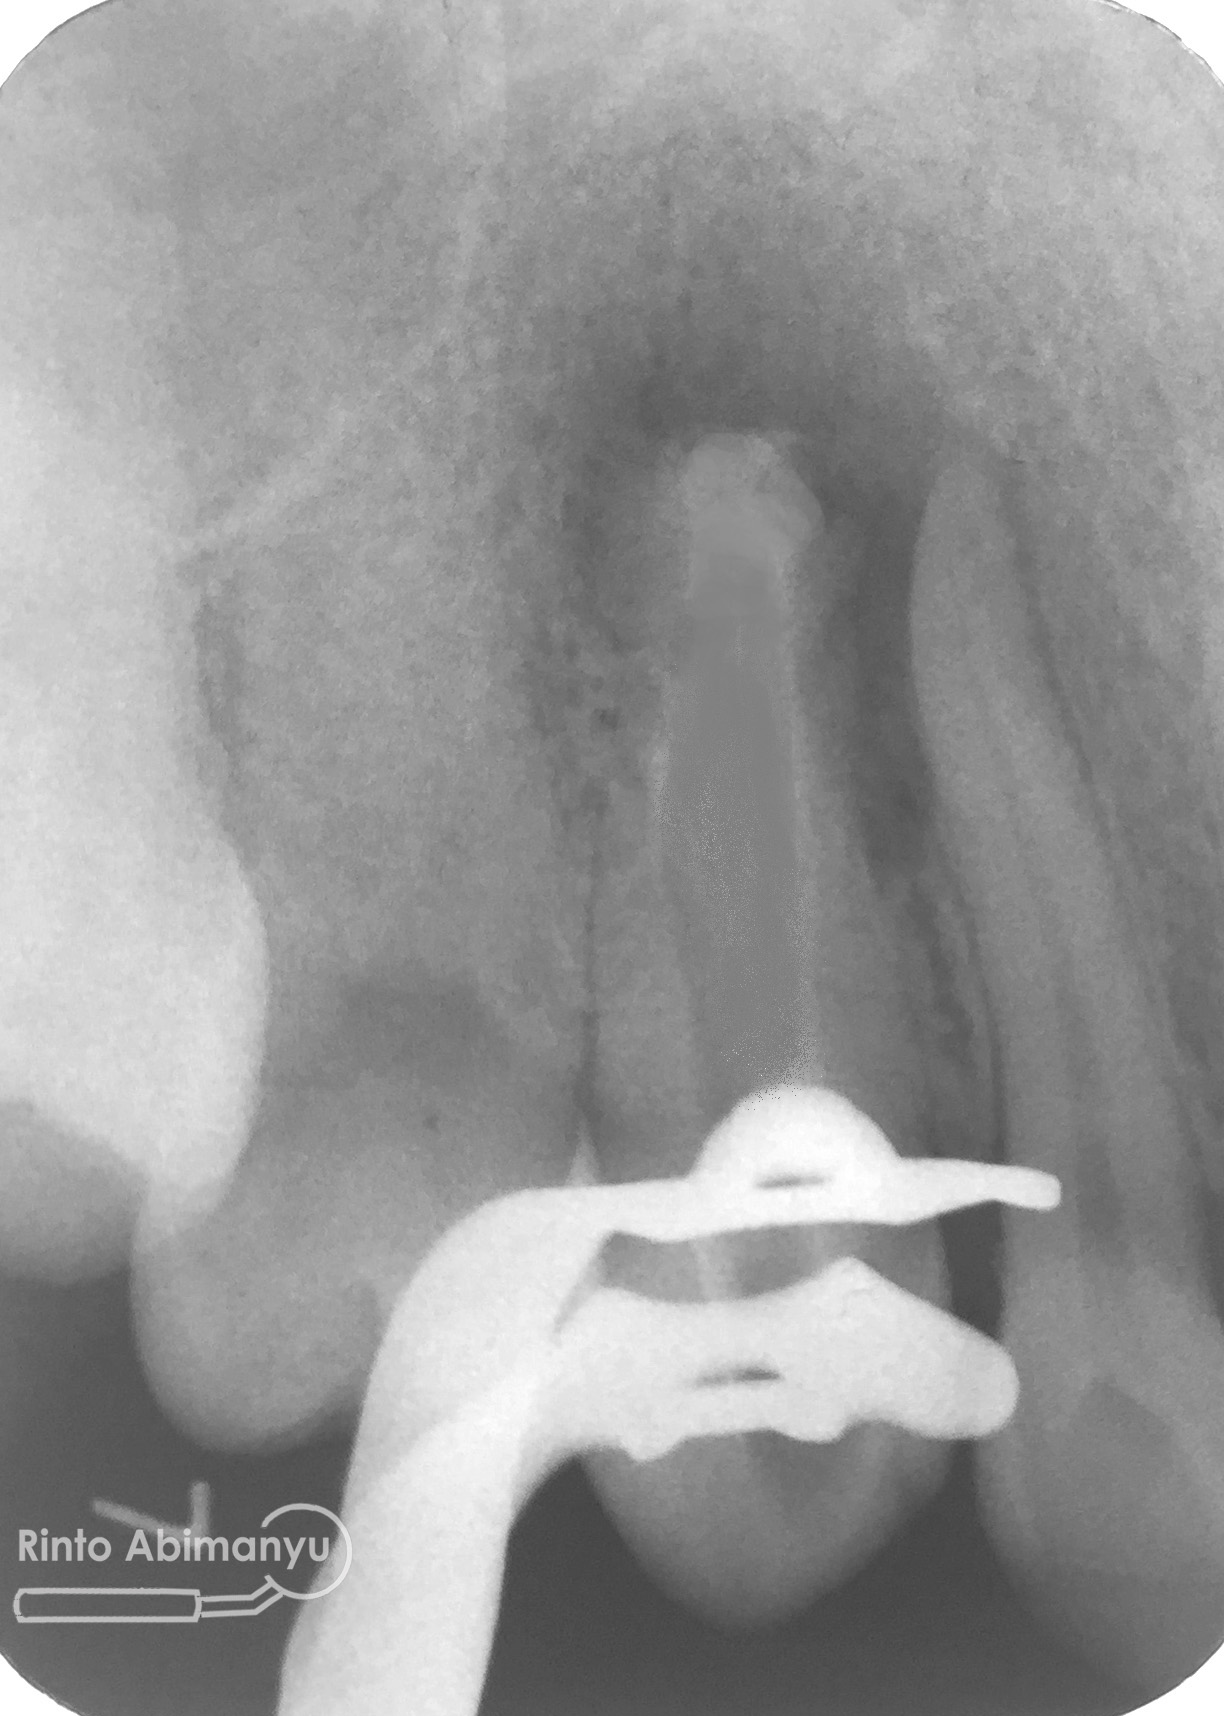

Setelah proses cleaning and shaping dilakukan trial gutta percha untuk melihat apakah kon utama yang akan kita gunakan pas dengan saluran akarnya…

Setelah melihat hasil ronsen trial guttap maka pengisian siap dilakukan… Untuk pengisian saluran akar saya memakai tehnik warm vertival condensation memakai alat Element Obturation Unit (SybronEndo) dan siler AH plus (Dentsply)…